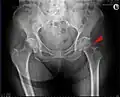

Mediale Schenkelhalsfraktur ohne Dislokation -

Laterale Schenkelhalsfraktur mit Adduktions-Dislokation -

Im Vergleich dazu ein gesundes Hüftgelenk